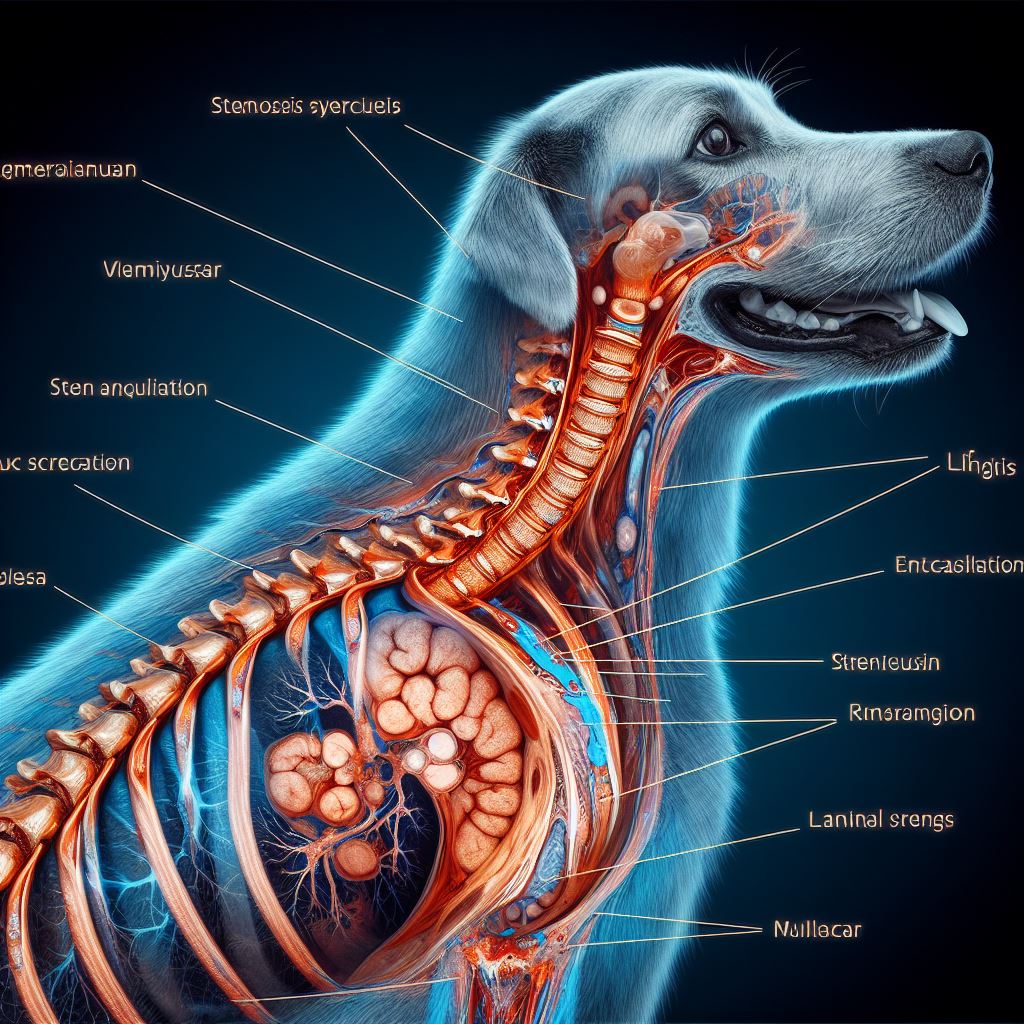

결론

강아지 기관지 협착증의 심각성

강아지 기관지 협착증은 호흡 곤란과 같은 심각한 증상을 유발하는 무시할 수 없는 질병입니다. 이 질병이 무시되거나 치료가 늦어지면 강아지의 일상 생활에 심각한 영향을 미치며, 때로는 생명을 위협할 수도 있습니다. 따라서, 이 질병의 존재를 인지하고 조기 발견, 그리고 적절한 치료가 중요합니다.

적극적인 관리와 예방의 중요성

강아지의 건강을 유지하고 증상을 예방하려면 정기적인 건강검진과 환경적 요인에 대한 주의가 필수적입니다. 건강 상태를 주기적으로 확인하고, 필요한 경우 전문가의 도움을 받아야 합니다. 또한, 강아지가 공기 오염이 심한 환경이나 스트레스 받는 환경에 노출되지 않도록 하는 것도 중요합니다.